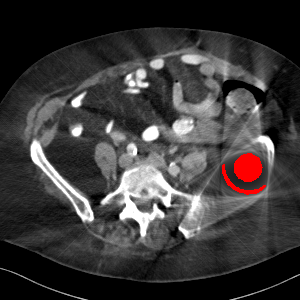

Visual comparison. As shown in Fig. 5, metallic implants such as spinal rods and hip prosthesis cause severe streaky artifacts and metal shadows, which obscure bone structures around them. cGan-CT cannot recover image intensity correctly for both cases. Sinogram domain or dual-domain methods perform much better than cGan-CT. LI, NMAR, and CNNMAR introduce strong secondary artifacts and distort the whole images. In NMAR images, there are fake bone structures around the metals, which is related to segmentation error in the prior image from strong metal artifacts. The segmentation error is also visible in NMAR sinogram. CNNMAR cannot restore the correct bone structures between rods in case 1. The tissues around the metals are over-smoothed in DuDoNet because LI sinogram and image are used as inputs, and the missing information cannot be inferred later. Our model retains more structural information than DuDoNet and generates anatomically more faithful artifact-reduced images.

Rating. Table 6 summarizes the ratings and P values for comparison between our model and the other methods. The performance of our model is significantly better than cGan-CT, LI, NMAR, CNNMAR on both datasets (all P values 0.03). Our model also achieves better ratings than DuDoNet.

Visual comparison. Fig. 7 shows two clinical CT images with metal artifacts. Case 1 is with moderate metal artifacts. cGan-CT does not suppress the artifacts completely and generates some fake details. LI, NMAR, CNN-MAR remove all the artifacts but introduce new streak artifacts, which is caused by the discontinuity in the corrected sinogram. DuDoNet outputs over-smoothed sinogram, which leads to blurred tissues close to the metal implants, such as muscle and bone. Only our model can provide realistic enhanced sinogram and remove the artifacts while retaining the structure of nearby tissues. Case 2 is very challenging as the rods bring strong metal shadows and bright artifacts around the vertebra. cGan-CT recovers the shape of vertebra but changes the overall image intensity. Other sinogram inpainting methods fail as the soft tissue and bone near the rods are heavily distorted. Our model removes part of the dark bands and reproduces correct anatomical structures around the rods.